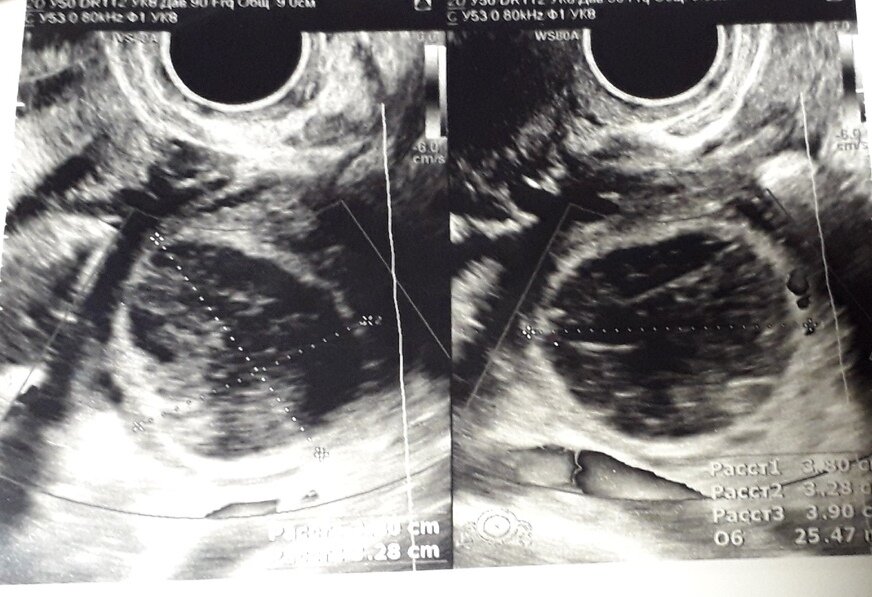

Та-да-да-дам...Настал тот самый момент... Тот самый момент, когда я узнаю точно, овулируют ли мои яичники. Фолликулометрия - это по сути то же самое УЗИ, только занимает меньше времени, так как смотрят только яичники. Эту процедуру нужно делать несколько месяцев подряд. Я сделала 3 раза (три цикла). 1 месяц: Есть овуляция! Ура! По словам врача, чуть ли не чудо из чудес. Но я была почти уверена, что все нормально у меня с овуляцией. 2 месяц: Тут я немного расстроилась, обнаружили функциональную кисту ( она же кистозно-измененное желтое тело). Но она исчезла сама к следующему циклу! (Между 2 и 3 фолликулометрией мне еще раз делали узи) 3 месяц: И опять она...Главное было ясно - овуляция есть! И это не могло не радовать.

Фолликулометрия - это по сути то же самое УЗИ, только занимает меньше времени, так как смотрят только яичники.

Эту процедуру нужно делать несколько месяцев подряд. Я сделала 3 раза (три цикла).

Тут я немного расстроилась, обнаружили функциональную кисту ( она же кистозно-измененное желтое тело). Но она исчезла сама к следующему циклу! (Между 2 и 3 фолликулометрией мне еще раз делали узи)